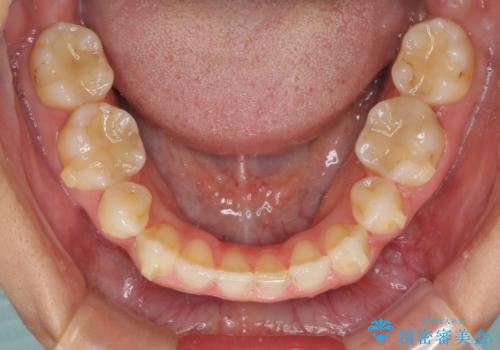

隙間の空いてしまった前歯は、矯正治療で治療を行っても後戻りが起こりやすい傾向にあります。

マウスピースの保定装置をしっかりと装着しても空いてしまうため、細いワイヤーによる保定を併用することで後戻りを防止しています。